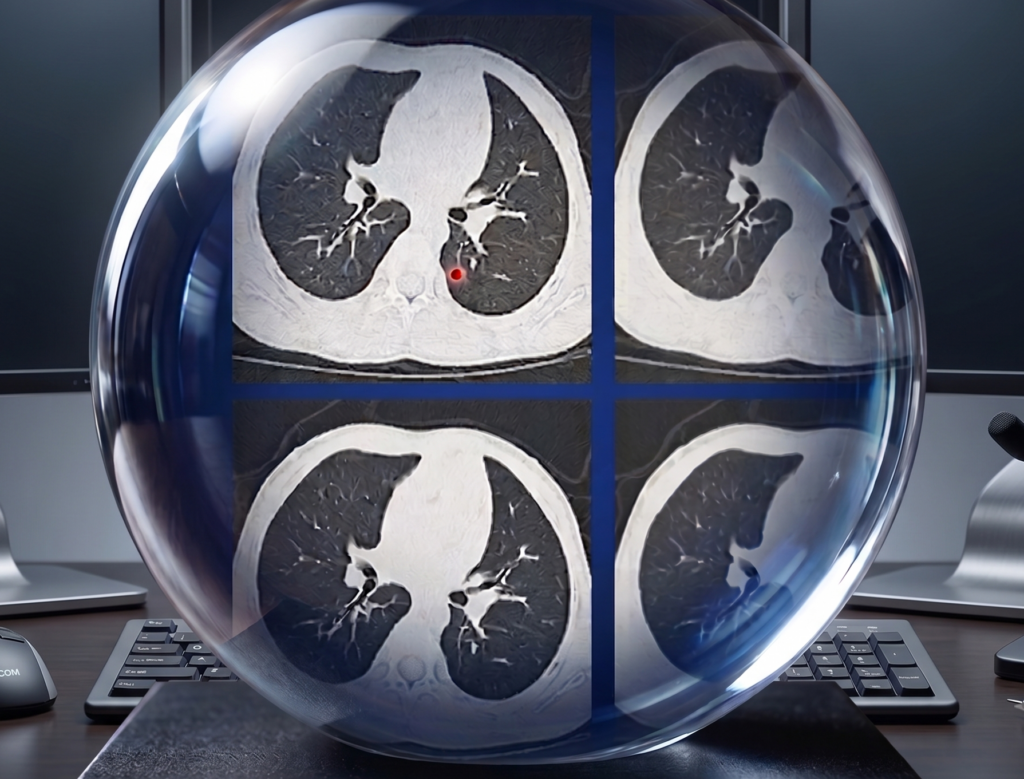

PCCT in Peds—Kernels of Truth

PCCT offers a massive leap in spatial resolution for detecting submillimeter metastatic nodules in children. But it isn’t a free lunch either.